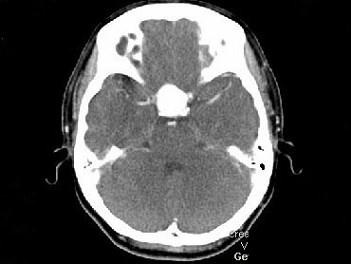

女,43岁,反复头痛10个月,CT检查如图,最可能诊断为 ( )A、脑膜瘤B、胶质瘤C、垂体瘤D、颈内动脉瘤E、颅咽管瘤

问题 女,43岁,反复头痛10个月,CT检查如图,最可能诊断为 ( )

选项 A、脑膜瘤 B、胶质瘤 C、垂体瘤 D、颈内动脉瘤 E、颅咽管瘤

答案 D